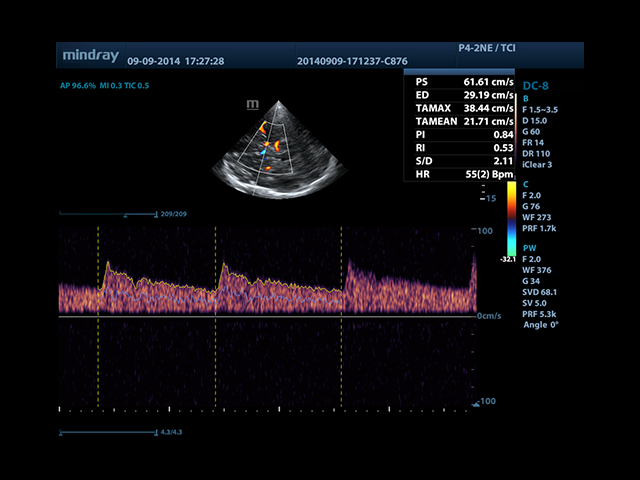

Mindray DC-8 Exp оснащен новым поколением датчиков с увеличенным количеством элементов и инновационной технологией "3T". Это позволяет достичь высокой детализации и качества изображения. Благодаря новейшей технологии iFlow, можно визуализировать даже самые мелкие сосуды и кровеносные пути.

• Smart Doppler - автоматическая подстройка расположения рамки цветового доплера и контрольного объема импульсно-волнового доплера нажатием кнопки.

• Автоматическая трассировка допплеровского спектра с расчетом параметров и индексов

• Smart Doppler™ - автоматическая подстройка расположения рамки цветового допплера и контрольного объема импульсно-волнового допплера